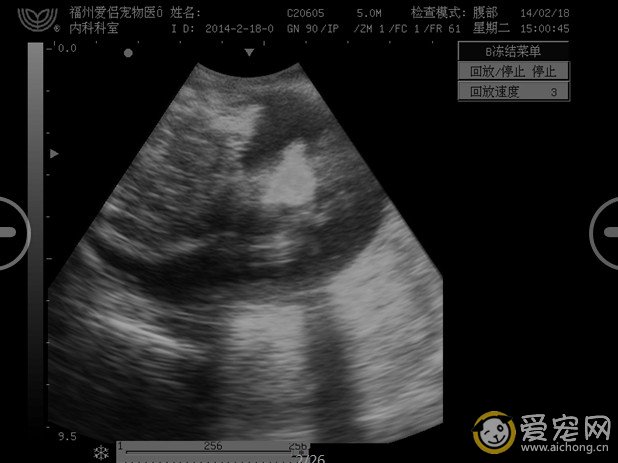

以下是一个难产的小鹿狗串,难产的原因是胎儿过大,而且第一次进入产道的胎儿胎位不正,看以下的图就知道怎么回事了。B超诊断能看到4个胎儿,但只有2个胎儿有心跳,其他第一第二进入产道的胎儿都确认死胎,没有心跳。